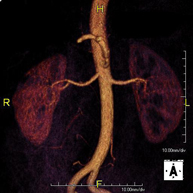

Prueba diagnóstica no invasiva que consiste en el estudio de la arteria aorta abdominal, obteniendo imágenes de alta definición anatómica mediante el empleo de un campo electromagnético y ondas de radio (con un emisor y un receptor). Es indispensable el uso de contraste paramagnético (Gadolinio). Sin embargo, no utiliza radiación ionizante. La calidad de las imágenes permite realizar reconstrucciones en 2D y 3D. Está indicado en aquellos pacientes con enfermedad vascular (aterosclerosis), estudio de aneurismas, en estudios pre-quirúrgicos de lesiones adyacentes a la aorta abdominal como "mapa" vascular, etc. - Angio RM Aorta-ilíaca

Prueba diagnóstica no invasiva que consiste en el estudio de la arteria aorta abdominal de las arterias ilíacas, obteniendo imágenes de alta definición anatómica mediante el empleo de un campo electromagnético y ondas de radio (con un emisor y un receptor). Es indispensable el uso de contraste paramagnético (Gadolinio). Sin embargo, no utiliza radiación ionizante. La calidad de las imágenes permite realizar reconstrucciones en 2D y 3D. Esta prueba está especialmente indicada como estudio pre-quirúrgico (mapa vascular) antes de intervenciones percutáneas o quirúrgicas de aorta abdominal y arterias ilíacas, estudio complementario en pacientes con isquemia de miembros inferiores, etc. - Angio RM Arterial extremidades inferiores

Prueba diagnóstica no invasiva que consiste en el estudio de la arteria aorta abdominal, obteniendo imágenes de alta definición anatómica mediante el empleo de un campo electromagnético y ondas de radio (con un emisor y un receptor). Es indispensable el uso de contraste intravenoso paramagnético (gadolinio). Sin embargo, no utiliza radiación ionizante. La calidad de las imágenes permite realizar reconstrucciones en 2D y 3D. Está indicado en aquellos pacientes con enfermedad vascular (aterosclerosis), estudio de aneurismas, en estudios pre-quirúrgicos de lesiones adyacentes a la aorta abdominal como "mapa" vascular… - Angio-RM Aorta iliaca

Prueba diagnóstica no invasiva que consiste en el estudio de la arteria aorta abdominal, obteniendo imágenes de alta definición anatómica mediante el empleo de un campo electromagnético y ondas de radio (con un emisor y un receptor). Es indispensable el uso de contraste intravenoso paramagnético (gadolinio). Sin embargo, no utiliza radiación ionizante. La calidad de las imágenes permite realizar reconstrucciones en 2D y 3D. Esta prueba está especialmente indicada como estudio pre-quirúrgico (mapa vascular) antes de intervenciones percutáneas o quirúrgicas de aorta abdominal, estudio complementario en pacientes con isquemia de miembros inferiores… - Angio-RM Arterias renales